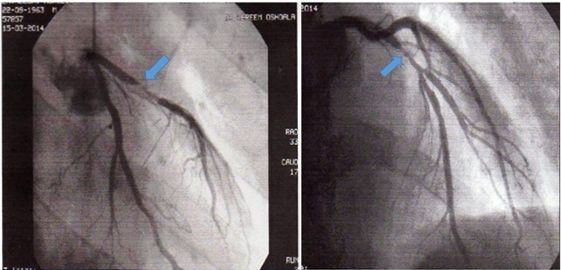

幸运的是,患者在一周后在另一家诊疗中心接受运动心电图检查,检查时发现了V4-V6导联ST段压低(图8),并伴有胸痛,表现为典型的心绞痛。恢复时,心电图仍提示V4-V6导联ST段明显压低(图9)。进一步安排了冠状动脉造影检查(图10),结果显示左前降支90%闭塞(TIMI 1级),后行血管成形术放置药物洗脱支架(DES)。患者在3个月后恢复正常的体力活动(骑车)。

图10 冠脉造影显示狭窄的前降支